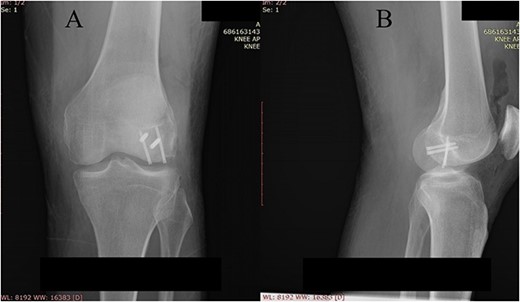

Postoperative plain X-ray of the left knee. (A) Anteroposterior view. (B) Lateral view.

One month after index surgery, the patient was readmitted for the second intervention. In spinal anesthesia, the left knee was positioned for routine arthroscopy. During the procedure, it was concluded that the achievement of proper anatomical fragment repositioning and fixation is unobtainable. Therefore, conversion to arthrotomy followed via the lateral parapatellar approach. Fragments were fixed with two titanium headless compression screws (3.5 mm) (Fig. 4). The second postoperative period was uneventful. Early range of motion exercises started on postoperative Day 2. The patient was discharged on postoperative Day 4. The rehabilitation period lasted 4 weeks. Weight-bearing was allowed at Week 8 after surgery.